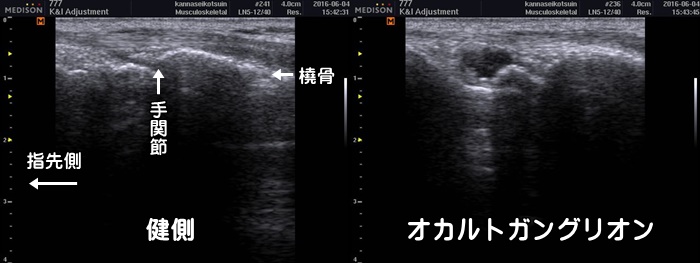

手首の甲のガングリオン

腕立て伏せのような形で手をつくと手首の甲側に痛みがある場合、ガングリオンが疑われます。ガングリオンは浅い所にできると体表からでも膨らみが確認できますが、上図の様に腱の下にできたオカルトガングリオンは体表からでは確認できません。レントゲンでは異常なしと言われます。通常ガングリオンは3年で約80%が自然消失します。